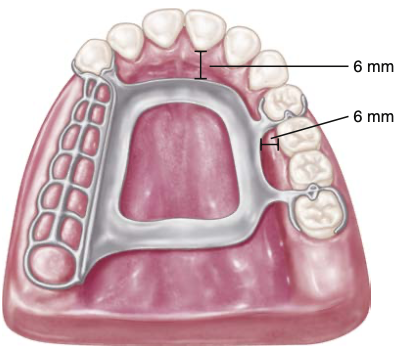

palatal major connector should be placed a minimum of 6mm away from and parallel to the gingival margins

palatal major connector [illustration]